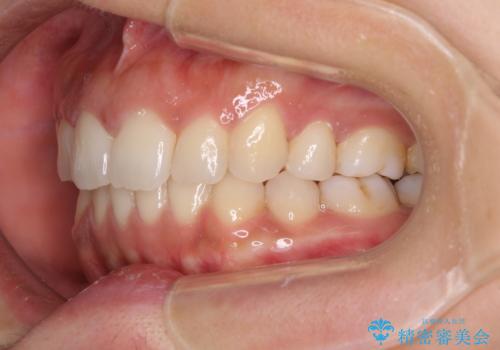

- 以前矯正治療をされていましたが、後戻りが起きたことを気にして来院された患者様です。

全顎的に認められた叢生を改善するため、インビザラインにて治療を行うこととしました。

前歯の叢生の改善を目的として、IPR(歯と歯の間を削る)と歯列全体の後方移動によって歯並びを整えることとしました。

臼歯部も含め、叢生が綺麗に改善され、患者様には大変満足していただきました。